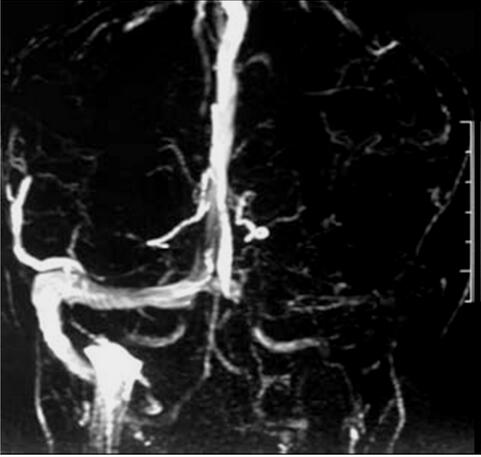

大脑中动脉慢性闭塞血管再通治疗经典案例1例

1小时条评论1 病例简介 患者男,64岁,因头昏、左下肢乏力3日入院。患者入院前3日无明显诱因逐渐出现持续性头部昏沉、伴左下肢乏力,行走时左下肢步态拖曳,无意识障碍,无视物成双,无视物旋转、恶心呕吐、饮水呛咳及肢体麻木等,于2010年1月5日入我院治疗。 既往史:2型糖...